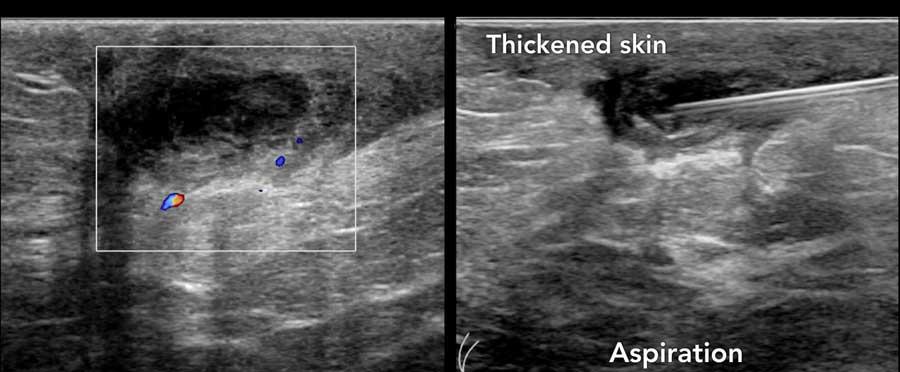

Hình ảnh cho thấy một tổn thương trống âm, có thể hơi giảm âm với thành hơi không đều và dày.

Tuy nhiên, vẫn có tăng âm phía sau, khiến chúng tôi nghĩ rằng đây có thể là một nang.

Chọc hút đã được thực hiện và nang được hút hoàn toàn, đây là bằng chứng cuối cùng xác nhận chẩn đoán.

Khi thấy có mạch máu trên siêu âm Doppler màu thì đó là khối u trong nang, có thể lành tính hoặc ác tính.

Đây là một khối u có thành phần dạng nang chứ không phải là một nang đơn thuần.

Trong trường hợp không có dòng chảy trên siêu âm Doppler màu và không có tín hiệu âm mức độ thấp di chuyển khi thay đổi tư thế bệnh nhân, cần thực hiện chọc hút để phân biệt giữa nang phức tạp và khối đặc.

Mủ và các mảnh vụn có thể được hút ra, khác với khối u.

Trong trường hợp này, sinh thiết xác nhận là ung thư biểu mô trong nang.

Đây là một trường hợp ung thư vú khác có thành phần dạng nang.

Lưu ý thành phần đặc lớn với dòng chảy trên hình ảnh Doppler.